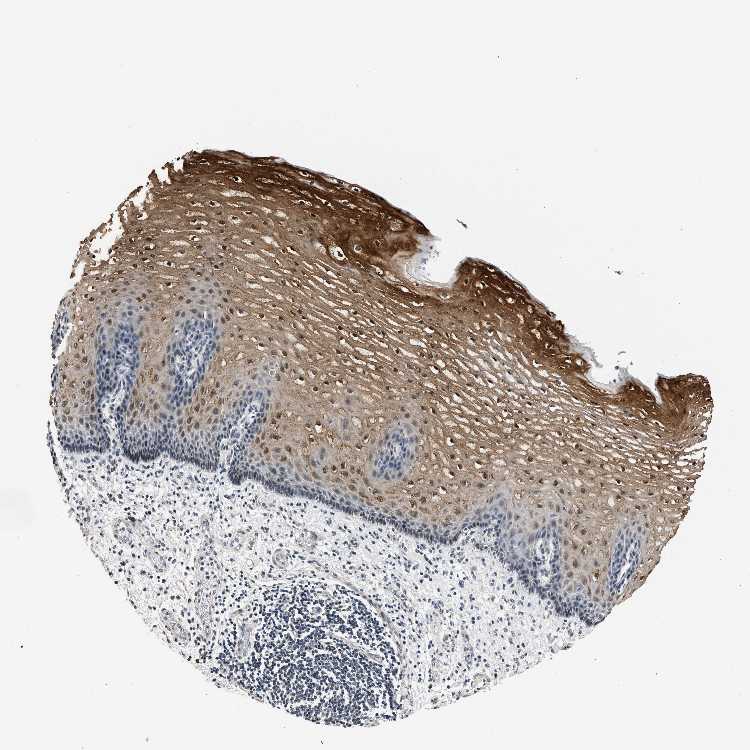

ESOPHAGUS - Antibody stainingi

Antibody staining in the annotated cell types in the current human tissue is reported as not detected, low, medium, or high, based on conventional immunohistochemistry profiling in selected tissues. This score is based on the combination of the staining intensity and fraction of stained cells.

Each image is clickable and will lead to virtual microscopy that enables deeper exploration of all samples and also displays staining intensity scores, fraction scores and subcellular localization as well as patient and tissue information for each sample.

Antibody HPA019232Antibody HPA021497Antibody HPA021768

Squamous epithelial cells HighLowHigh